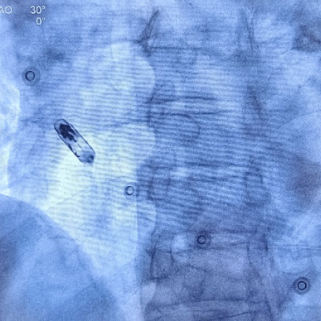

心房无导线起搏器最终植入位置

手术首先利用电生理四极导管标测Bachmann束区域,留影做参考;再次利用保护套筒造影精准确认植入位置,后退保护套筒,将心房无导线旋入1.5圈,参数良好且稳定。